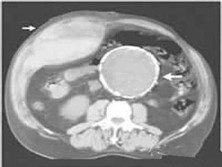

腹直肌鞘內(nèi)血腫(腹直肌鞘內(nèi)血腫)

腹直肌鞘內(nèi)血腫

腹直肌位于腹白線(腹正中線)的兩側(cè),被腹直肌鞘整個包裹在內(nèi)。腹直肌有3~4個腱劃,與腹直肌鞘的前層緊密黏著,而與腹直鞘后層不黏著,腱劃處有血管。腹壁上動脈,是胸廓內(nèi)動脈的終支,在腹直肌鞘內(nèi)沿腹直肌后面下降。腹壁下動脈,自髂外動脈發(fā)出,最后進入腹直肌鞘在腹直肌后面與腹壁上動脈吻合。腹直肌后的血管在某種因素(外力或腹壓等)... [詳情]